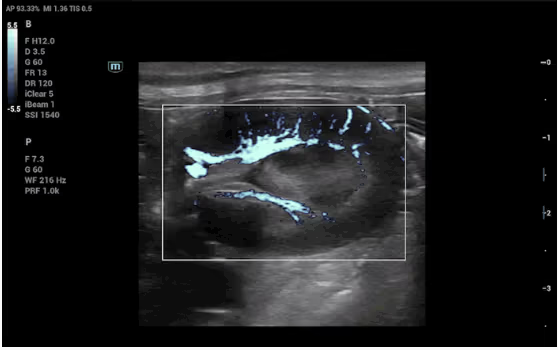

Mindray Animal'a özgü özel işleme algoritmasına dayanan bu yenilikçi teknoloji, küçük damarları ve karmaşık akış paternlerini daha iyi görüntülemek için geliştirilmiştir.